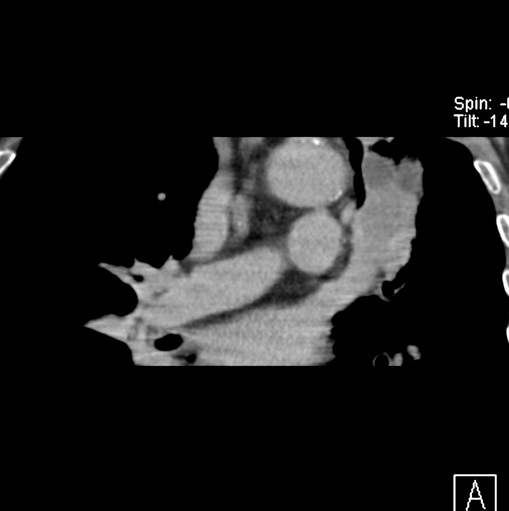

男性患者 81岁 咳嗽 咳痰 咯血

肿块贴近左肺门,包绕左上肺动脉,形态不规则。肿块增强扫描中度强化。纵膈内主动脉弓左旁间隙、气管隆突前、下间隙见多枚淋巴结影。综上考虑左侧中央型肺癌可能性大。图片没有完整上传,尤其是左肺上叶支气管分支层面没有上传,因此不好判断是叶支气管中断还是段支气管中断。另外,下图红色部分所示是“黏液支气管征”吗?